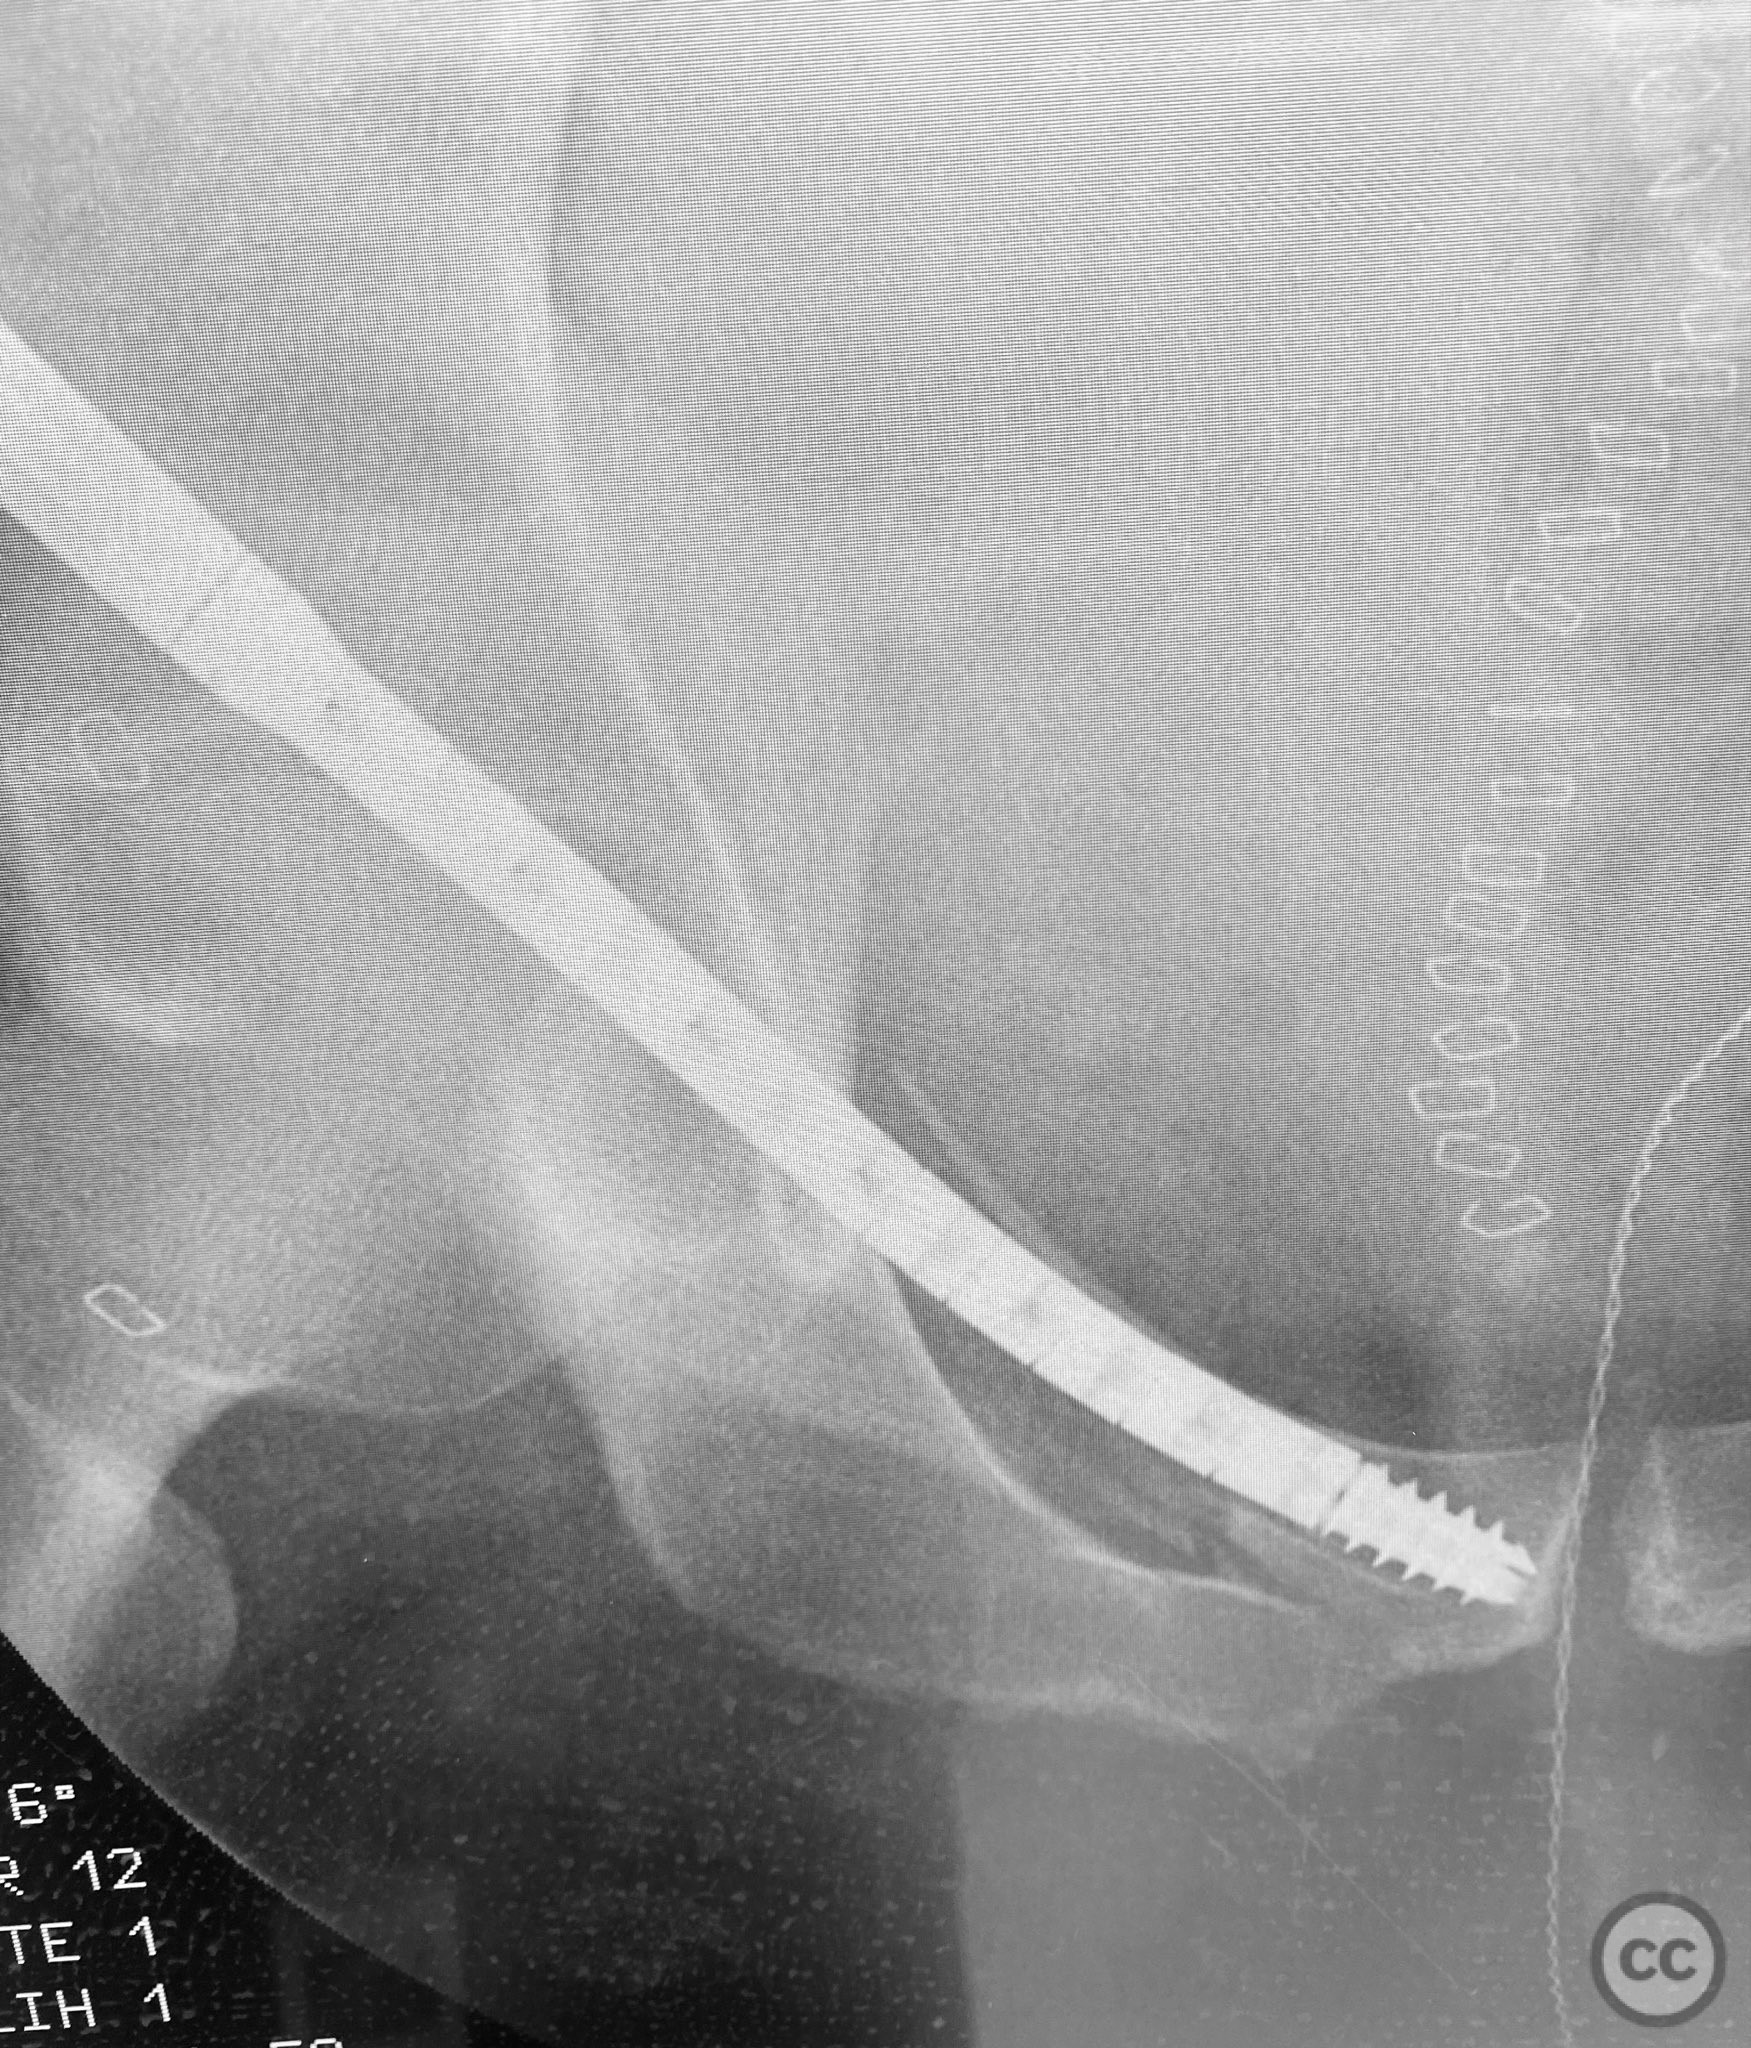

Pelvic Ring - AO/OTA 61x

Percutaneous Screw Fixation of AO/OTA 61...

Texas, United States

Pelvis - AO/OTA 6x

Percutaneous CurvaFix Fixation for Pelvi...

Percutaneous Screw Fixation for Pelvic R...

Percutaneous CurvaFix Fixation of Obliqu...

Trans-symphyseal Screw Fixation for Unst...